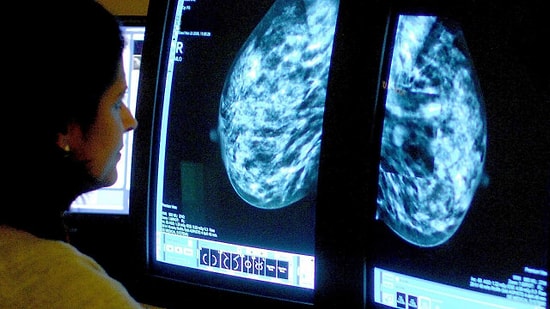

NantHealth isimli bir şirket kanserle savaşmak için genom tarayıcı sistemi geliştiriliyor. Şirketin iş ortakları arasında BlackBerry de var.NantHealth CEO’su Patrick Soon-Shiong‘un yaptığı açıklamaya göre kanser ile mücadelede önemli bir yola girilmiş olabilinir. CEO’ya göre hem tedavi hem de teşhis için çok mühim bir çalışma yürütülüyor. Soon-Shiong’un çalışması sayesinde doktorlar hastaların durumunu gerçek zamanlı olarak takip edebilecek ve kanser genom tarayıcısı ile her bir detayı izleyebilecek.BlackBerry ile ortak yürütüldüğü söylenen projede hasta herhangi bir doku parçası gönderecek. Süperbilgisayarlar tarafından taranan doku örnekleri anormal gen mutasyonlarını anında tespit ederek hangi ilacın verilmesi gerektiğine dair önemli bir yol gösterici görevi görecek. Bu işlemleri Google Maps servisine benzeten Soon-Shiong, yanlış adres hatalı tedaviya yönelme ve kanserin yayılması anlamına gelecektir diyor.Analiz sürecinde tüm genomun incelenmesi ve proteine kadar tüm detayların görüntülenmesi bu sayede artık mümkün olacak. Günde 4 bine yakın hastanın taramasını gerçekleştirebildiklerini belirten Patrick Soon-Shiong, toplamda 1.2 milyar dolar harcandığını ve dış yatırımcılardan NantHealth‘in yaklaşık 250 milyon dolar aldığını söylüyor.BlackBerry ile güvenlik için de anlaştıklarının altını çizen CEO, şimdiye kadar bu iş için herhangi bir ekosistemin yaratılmadığını, bunu kendilerinin gerçekleştirmeye başladıklarını ve hastaların hayati verilerini, nabız ve sıcaklıklarını takip etmek icap ettiğinden bahsediyor.Büyük Veri konusunun da kendileri için oldukça önemli olduğunun altını çizen CEO Patrick Soon-Shiong, tek bir hastanın genom bilgilerinin neredeyse 500 GB tuttuğunu, 10 bin ya da milyonlarca hastanın ise zettabyte’larca içerik anlamına geldiğini belirtiyor. Teknolojik yeterlilik açısından ilk önce Amerika, Kanada ve İngiltere’de işe başlayacaklarını söyleyen yönetici, her bir ülkenin kendine has kişisel gizlilik kuralı olduğunu da bildiklerinden bahsediyor.Shiong’un söylediği son şey ise oldukça ümit verici: “Hedefimiz kanseri sıradan, kronik bir hastalık seviyesine çekebilmek”.TechInside